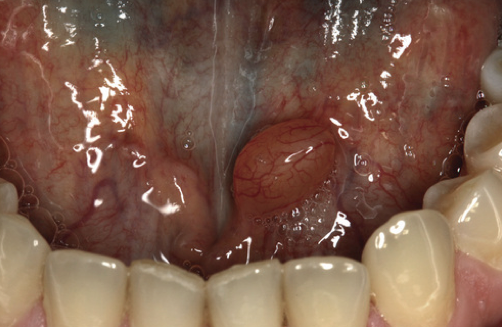

What is the likely Dx?

Mucocele.